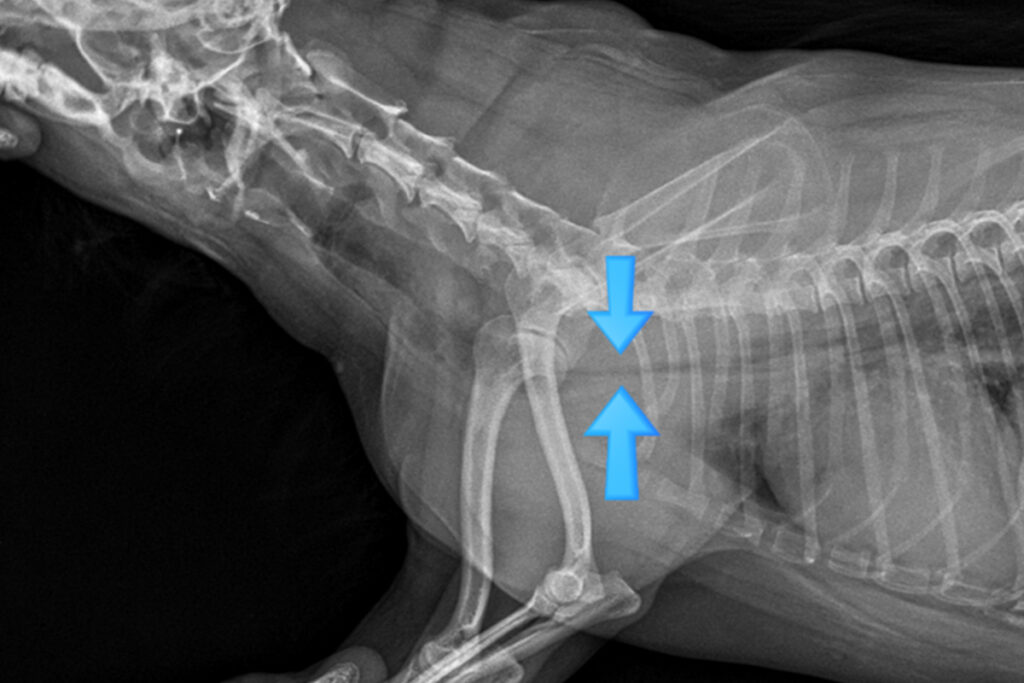

호흡기 내과

기침, 호흡 곤란, 숨소리 변화는 생명을 위협할 수 있는 중요한 증상입니다. 기도, 폐, 흉강 질환을 면밀히 평가해 호흡 상태에 맞춘 치료와 관리 계획을 세웁니다.